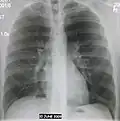

A black and white X-ray picture showing a triangle white area on the left side. A circle highlights the area.

A chest X-ray showing a very prominent wedge-shape bacterial pneumonia in the right lung